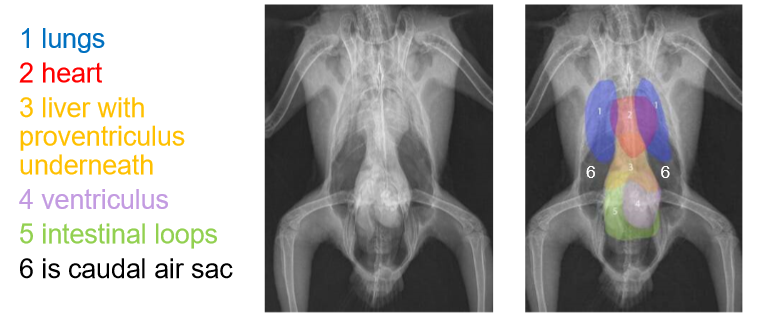

• label the image

A) lungs

B) heart

C) liver

D) ventriculus

E) intestines

F) caudal